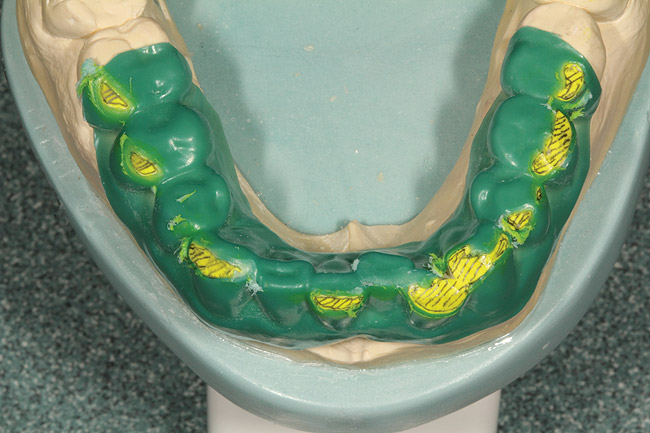

After the diagnostic models were poured and based, they were mounted using CR bites and an earless facebow (Kois Dento-Facial Analyzer, Panadent, www.panadent.com) with the Stratos/Kois mounting table on a Stratos 200 articulator. A green plastic suck-down material (LAK Enterprises, www.lakdental.com) was vacuum-formed over the preoperative model (Figure 10 and Figure 11). Any dentition protruding from the arch form (labially or lingually) was reduced, creating a reduction stent used intraorally so the dentition could conform to the proper arch form. The preparations were completed and the final margin positions were established and smoothed with the KS3SC, KS5SC, KS6SC, and 8856.021 burs (Komet USA, www.kometusa.com).

Figure 10  A green plastic reduction stent was vacuum-formed over the preoperative upper model.

Figure 10

Figure 11  The reduction guide was created.

Figure 11